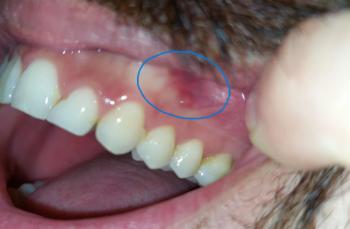

The image shows red, swollen, and darkened gum tissue below the lower front teeth. The gums appear inflamed and slightly enlarged, with a darker coloration that suggests active gum irritation or early infection. The teeth themselves look mostly intact, but the gum condition indicates a problem at the gumline.

This type of issue is often noticed when the lip is pulled down and may be accompanied by tenderness or bleeding.

This case shows inflamed lower front gums with healthy teeth, a very common condition. With early professional cleaning and good home care, gum health can be fully restored.